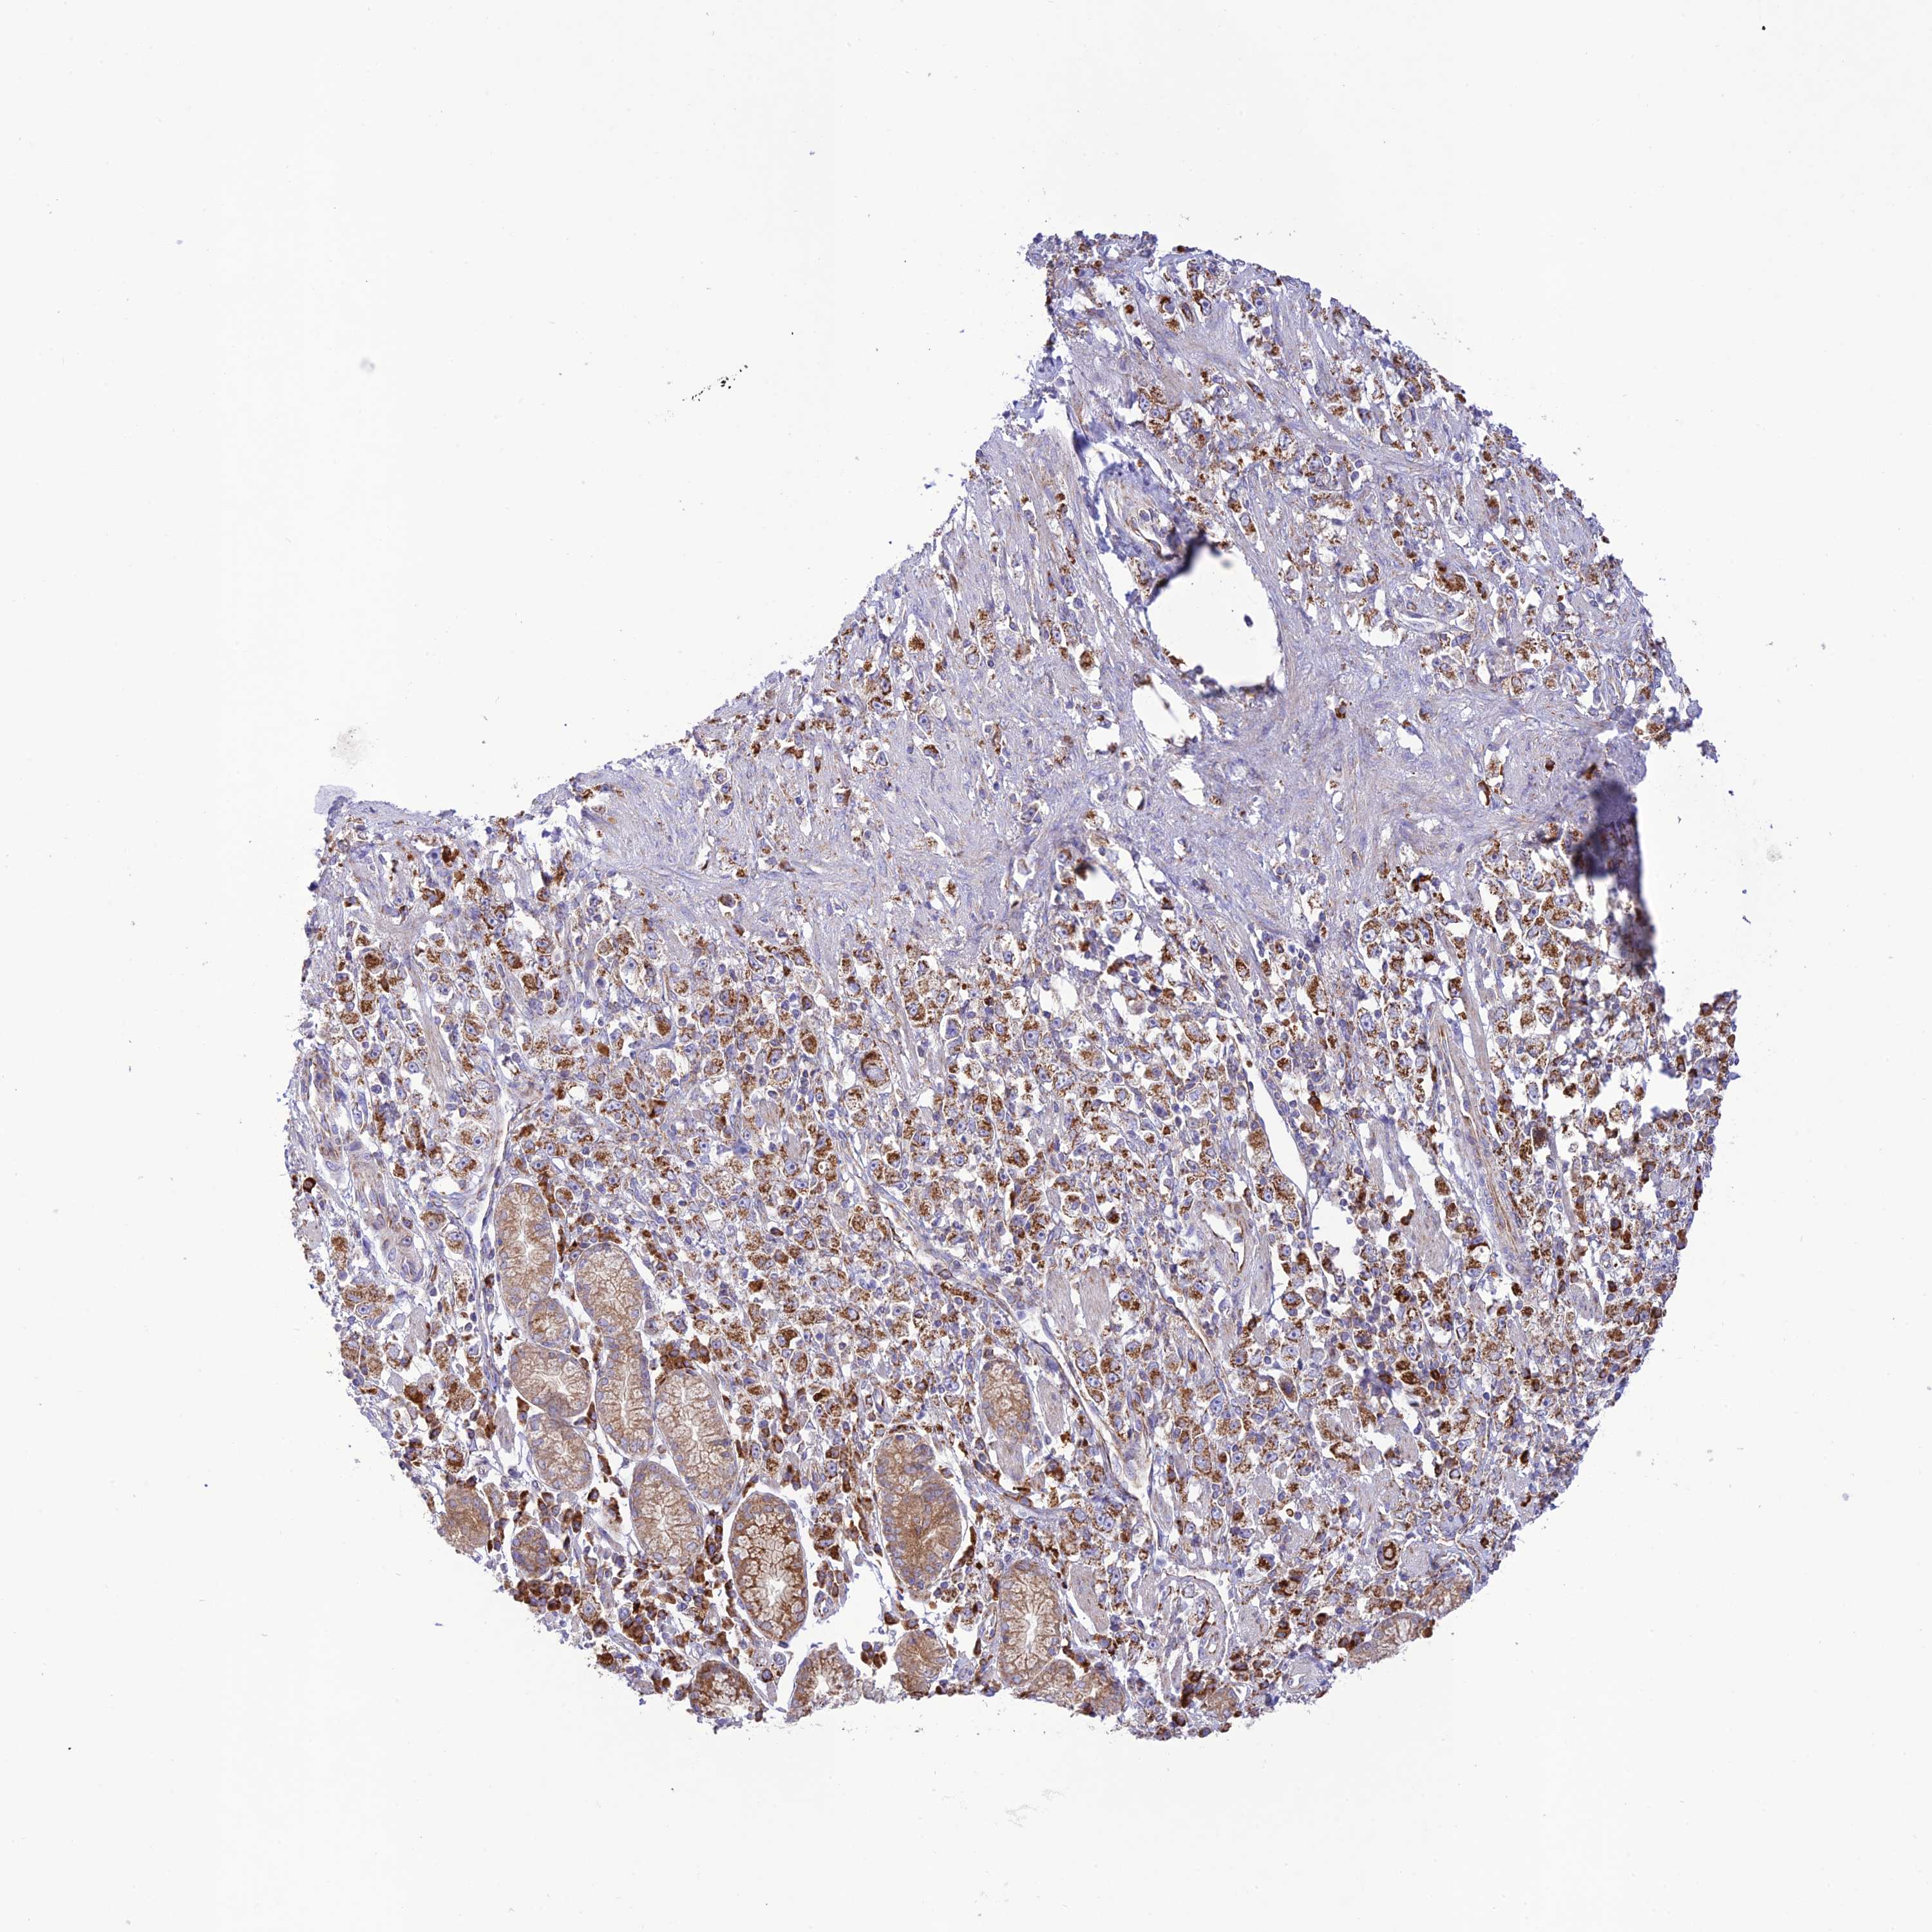

STOMACH CANCER - Protein expressioni

A mouse-over function shows sample information and annotation data. Click on an image to view it in a full screen mode. Samples can be filtered based on level of antibody staining by selecting one or several of the following categories: high, medium, low and not detected. The assay and annotation is described here.

Note that samples used for immunohistochemistry by the Human Protein Atlas do not correspond to samples in the TCGA dataset.

Antibody stainingi

Antibody staining in the annotated cell types in the current human tissue is reported as not detected, low, medium, or high, based on conventional immunohistochemistry profiling in selected tissues. This score is based on the combination of the staining intensity and fraction of stained cells.

Each image is clickable and will lead to virtual microscopy that enables deeper exploration of all samples and also displays staining intensity scores, fraction scores and subcellular localization as well as patient and tissue information for each sample.

Antibody HPA044356

Staining

High

Medium

Low

Not detected

Intensity

Strong

Moderate

Weak

Negative

Quantity

>75%

75%-25%

<25%

None

Location

Nuclear

Cytoplasmic/membranous

Cytoplasmic/membranous,nuclear

Adenocarcinoma, NOS